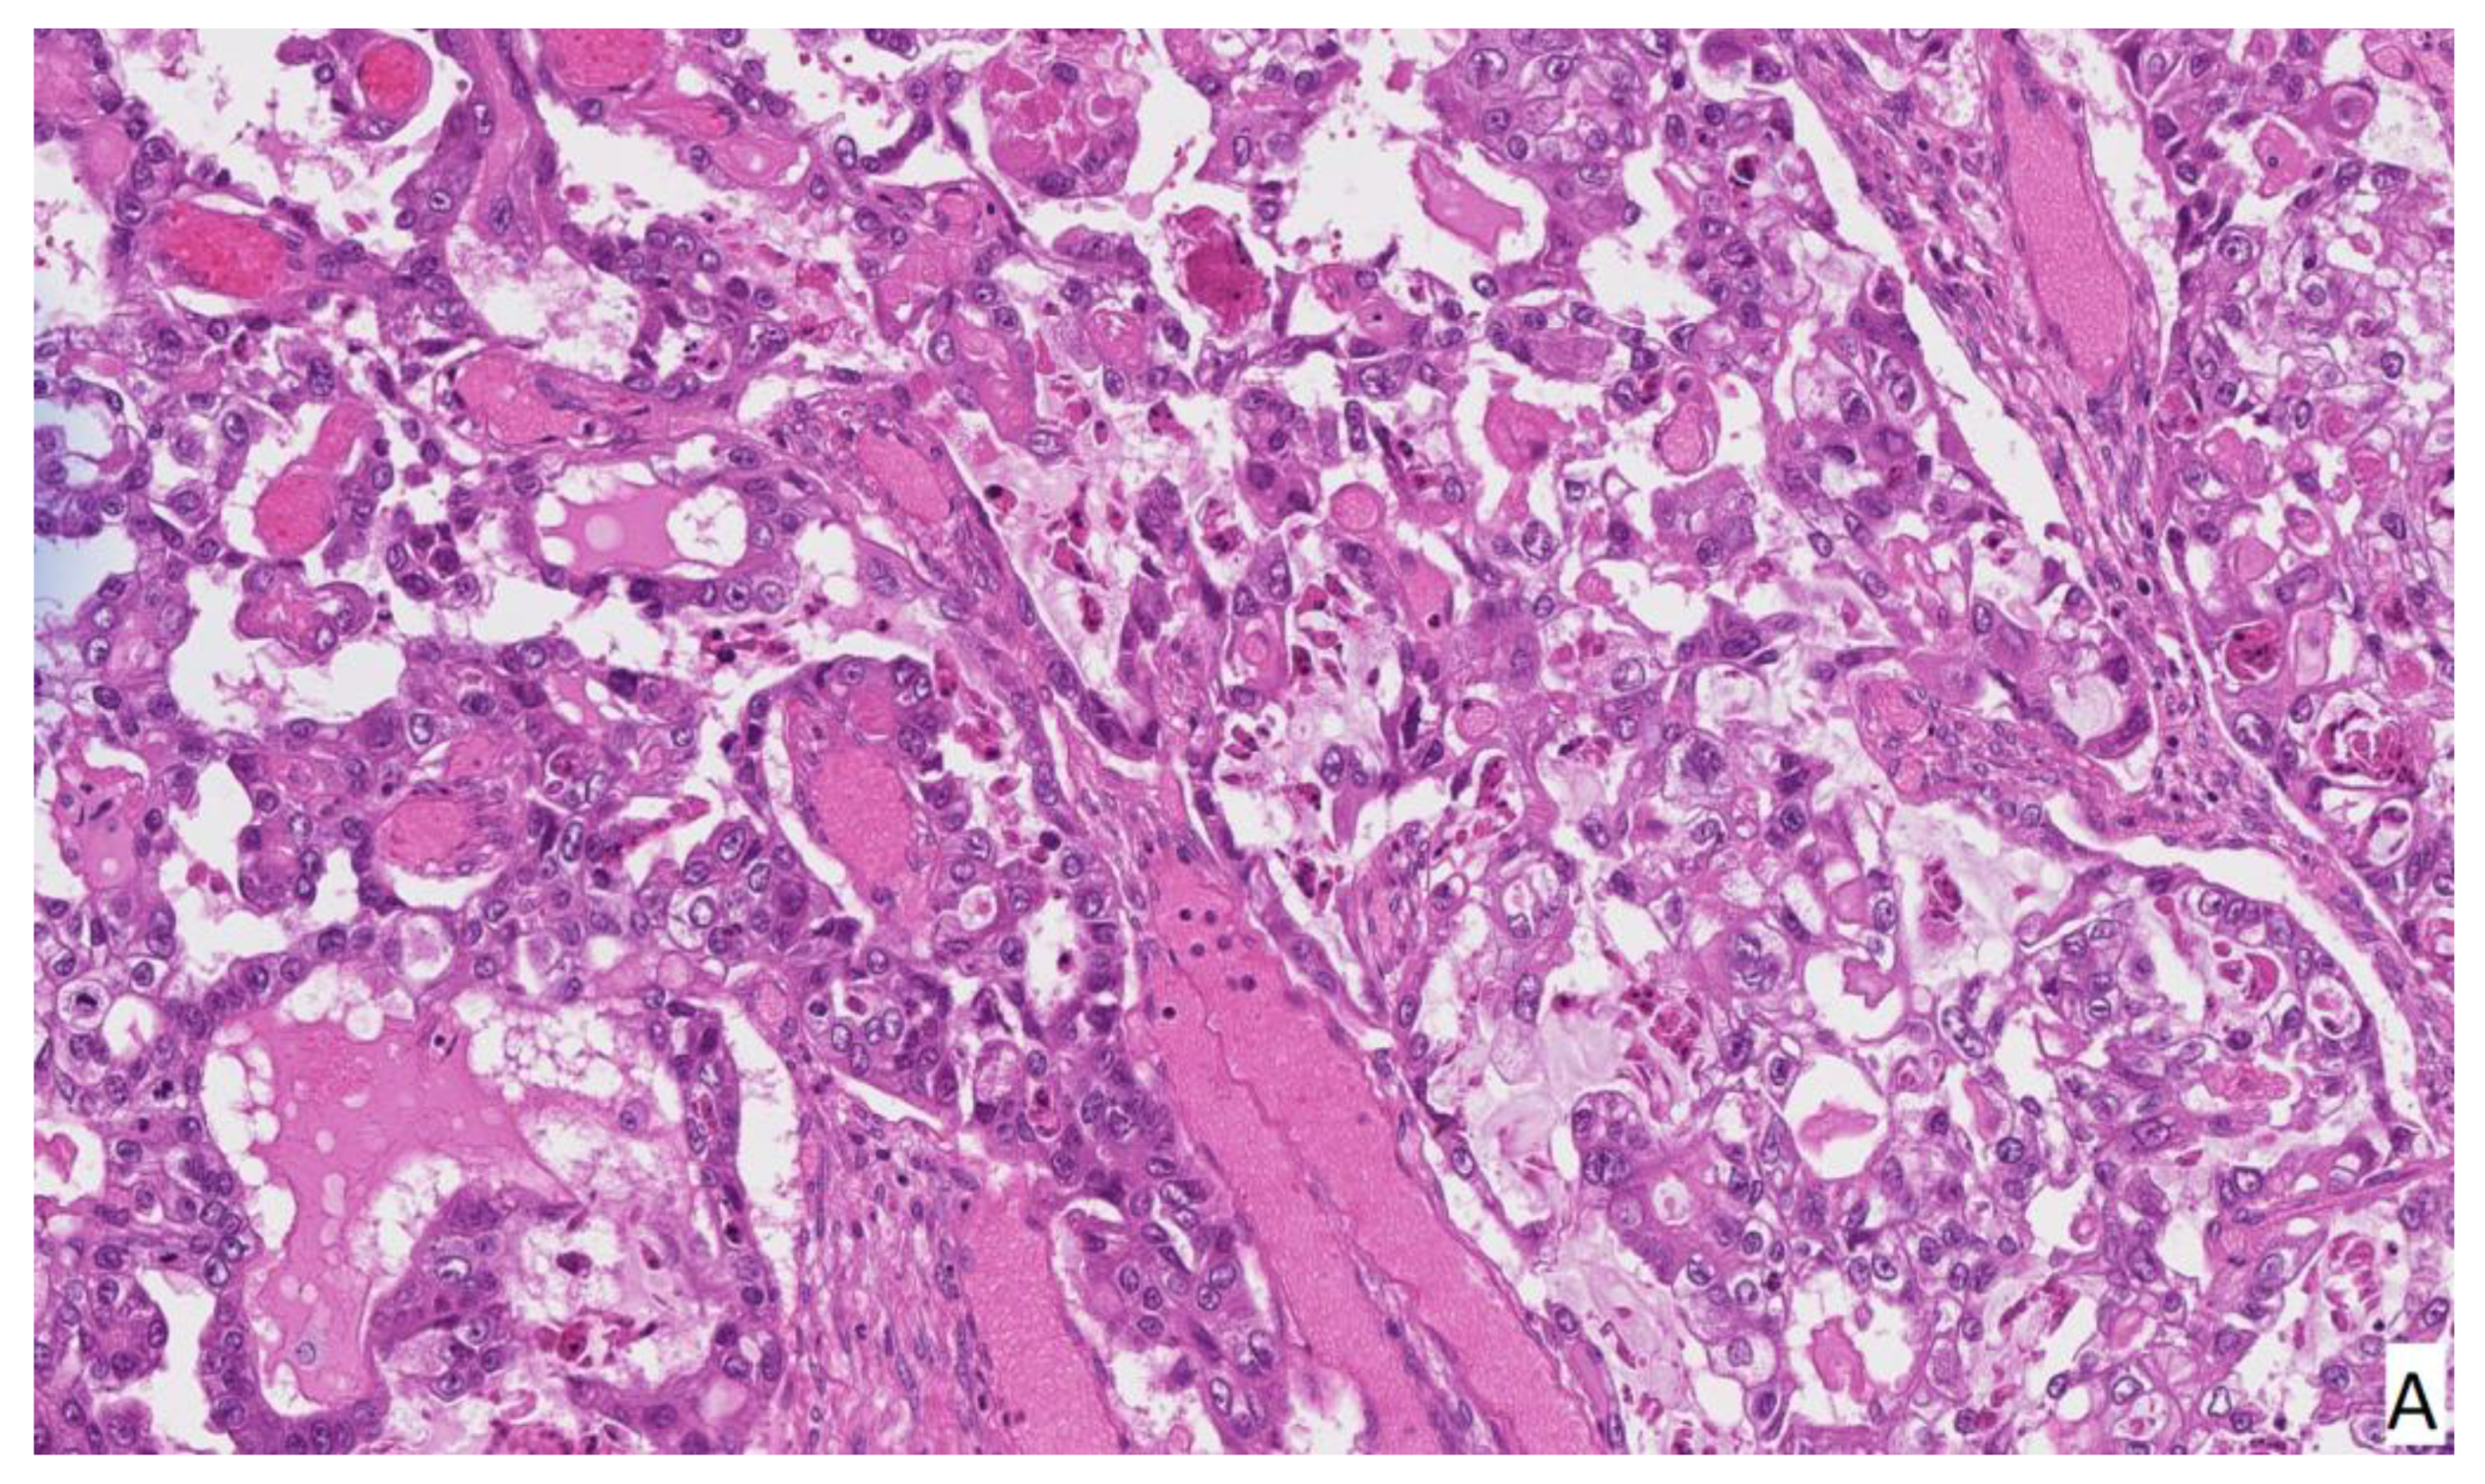

The patient left the operating room in stable condition and recovered uneventfully. She was discharged from the hospital after five days of hospitalization without any postoperative complications. Histological examination revealed right ovary clear cell carcinoma TNM stage pT1a with endometrioid gland and stroma formations in the ovary. Clear cell carcinoma phenotype: NapsinA (+++), P53 (+), p16 (++), WT1 (−), HNf-1B (−), SALL4 (−), OCT4 (−) (Figure 3).

Figure 3.

Histopathology of clear cell carcinoma. H&E staining (A) shows variation between cells with clear and light eosinophilic cytoplasm. Immunohistochemistry immunoprofile is Wilms tumor 1 (WT-1) negative (B), p-53 positive (C), HNF1beta negative (D), Napsin-A positive (E) tumor. Alcian blue/periodic acid–Schiff (AB/PAS) staining (F) shows glycogen in clear cells.